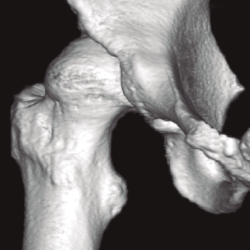

Retiraremos los osteofitos con una fresa desde la unión capsulolabral para movernos más cómodos y seguiremos con la resección del os labrale, osteofito o labrum calcificado (Figura 3).

Figura 3. Paciente con osteofito en el reborde acetabular (imagen izquierda). Resección del osteofito en el reborde acetabular (imagen derecha).